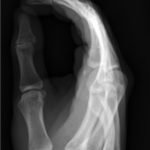

A two-view radiograph of the right hand was obtained which revealed a dorsal dislocation of the distal fourth and fifth metacarpals (see red and blue outline, respectively) with a concomitant fracture of the distal fifth metacarpal (see yellow line) and avulsion fracture of the lateral aspect of the hamate (see green line). After reduction the fourth and fifth metacarpal dislocations are resolved; however, the distal fifth metacarpal fracture (yellow line) and avulsion fracture of the lateral aspect of the hamate (green line) are still visible.

In a case series including 21 patients, dorsal dislocation of carpometacarpal joints was initially missed in 15 of these cases.1 This is often due to the overall swelling that may mask the ulnar deformity as well as failure to obtain a true lateral X-ray.This is a rare injury because there are many strong supporting ligaments.2 The dislocation requires closed reduction, with application of ventral longitudinal pressure and traction of fourth and fifth digit.3 There is debate amongst hand surgeons if closed reduction followed by casting or open reduction is superior, but there have been no large-scale studies comparing treatment options.4 Post-reduction films were obtained and an ulnar gutter splint was placed. The patient was instructed to follow up with hand surgery in the next week.